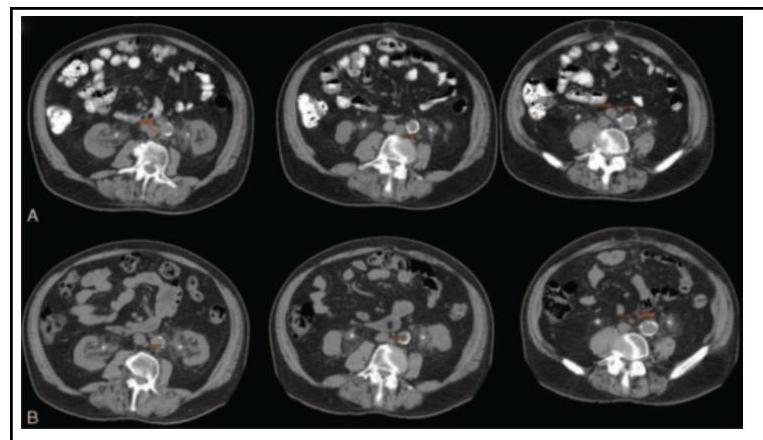

Explanation: ***CT scan*** - The image shows multiple **axial slices** with detailed cross-sectional anatomy of the abdomen, which is characteristic of a **Computed Tomography (CT) scan**. - CT scans provide excellent detail of both **soft tissues** and **bone structures** in cross-sectional format, which is the standard appearance of abdominal CT imaging. *X-ray* - Plain X-rays produce **2D projection images**, not the axial cross-sectional slices seen here. - While CT technology uses X-rays, in medical terminology **"X-ray"** refers to conventional radiographs, not cross-sectional imaging. *Contrast Dye study* - This is **not an imaging modality** but rather an enhancement technique used with various imaging methods. - **Contrast agents** improve visualization but don't define the type of investigation being performed. *Angiography* - Angiography is specifically designed to visualize **blood vessels**, often using contrast injection. - This image shows comprehensive **abdominal anatomy**, not the focused vascular imaging typical of angiographic studies.